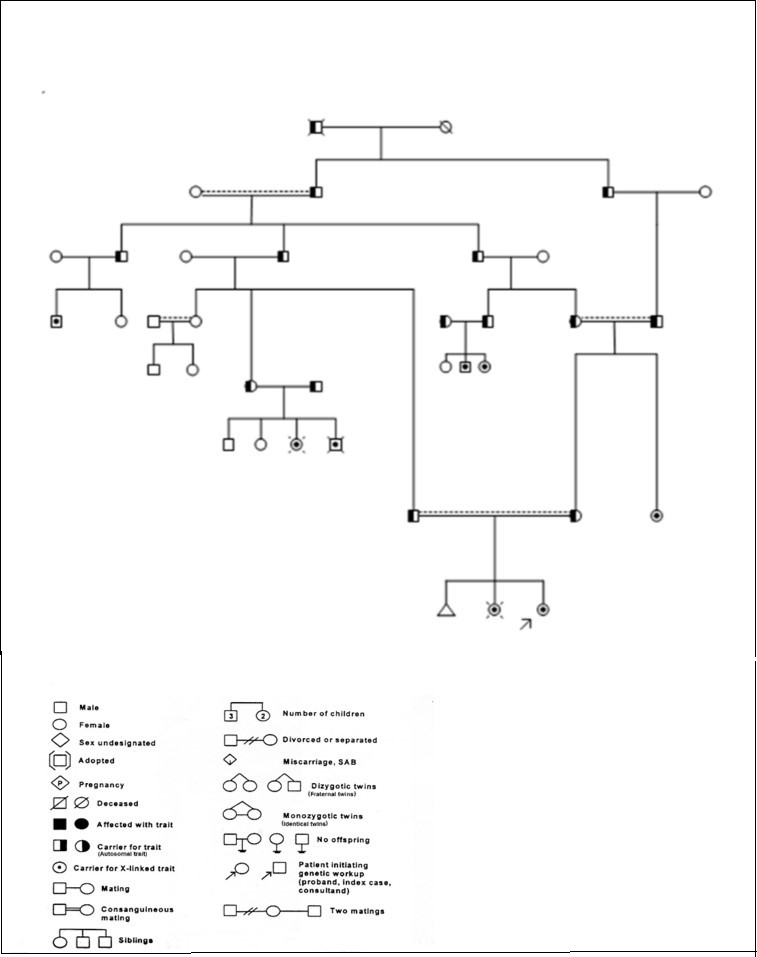

The patient was the third child of a consanguineous marriage. The first child aborted in the third month of the pregnancy and the second child revealed EVC syndrome manifestations – short stature, six-fingered, heart disease and nails deformity – and died at the age of six months because of bacterial meningitis. The Mother, at the age of twenty one, gave birth to the third child with three and a half kilograms of weight, 49 cm height, head circumference of 38 cm, and appearance of a natural person through a vaginal delivery. In the family tree of the patient (Graph1), this syndrome has occurred in eight people, the closest one was her 24-year-old aunt who did not cooperate for interview and examination, but her parents were healthy. The patient has normal intelligence and educates in regular schools.